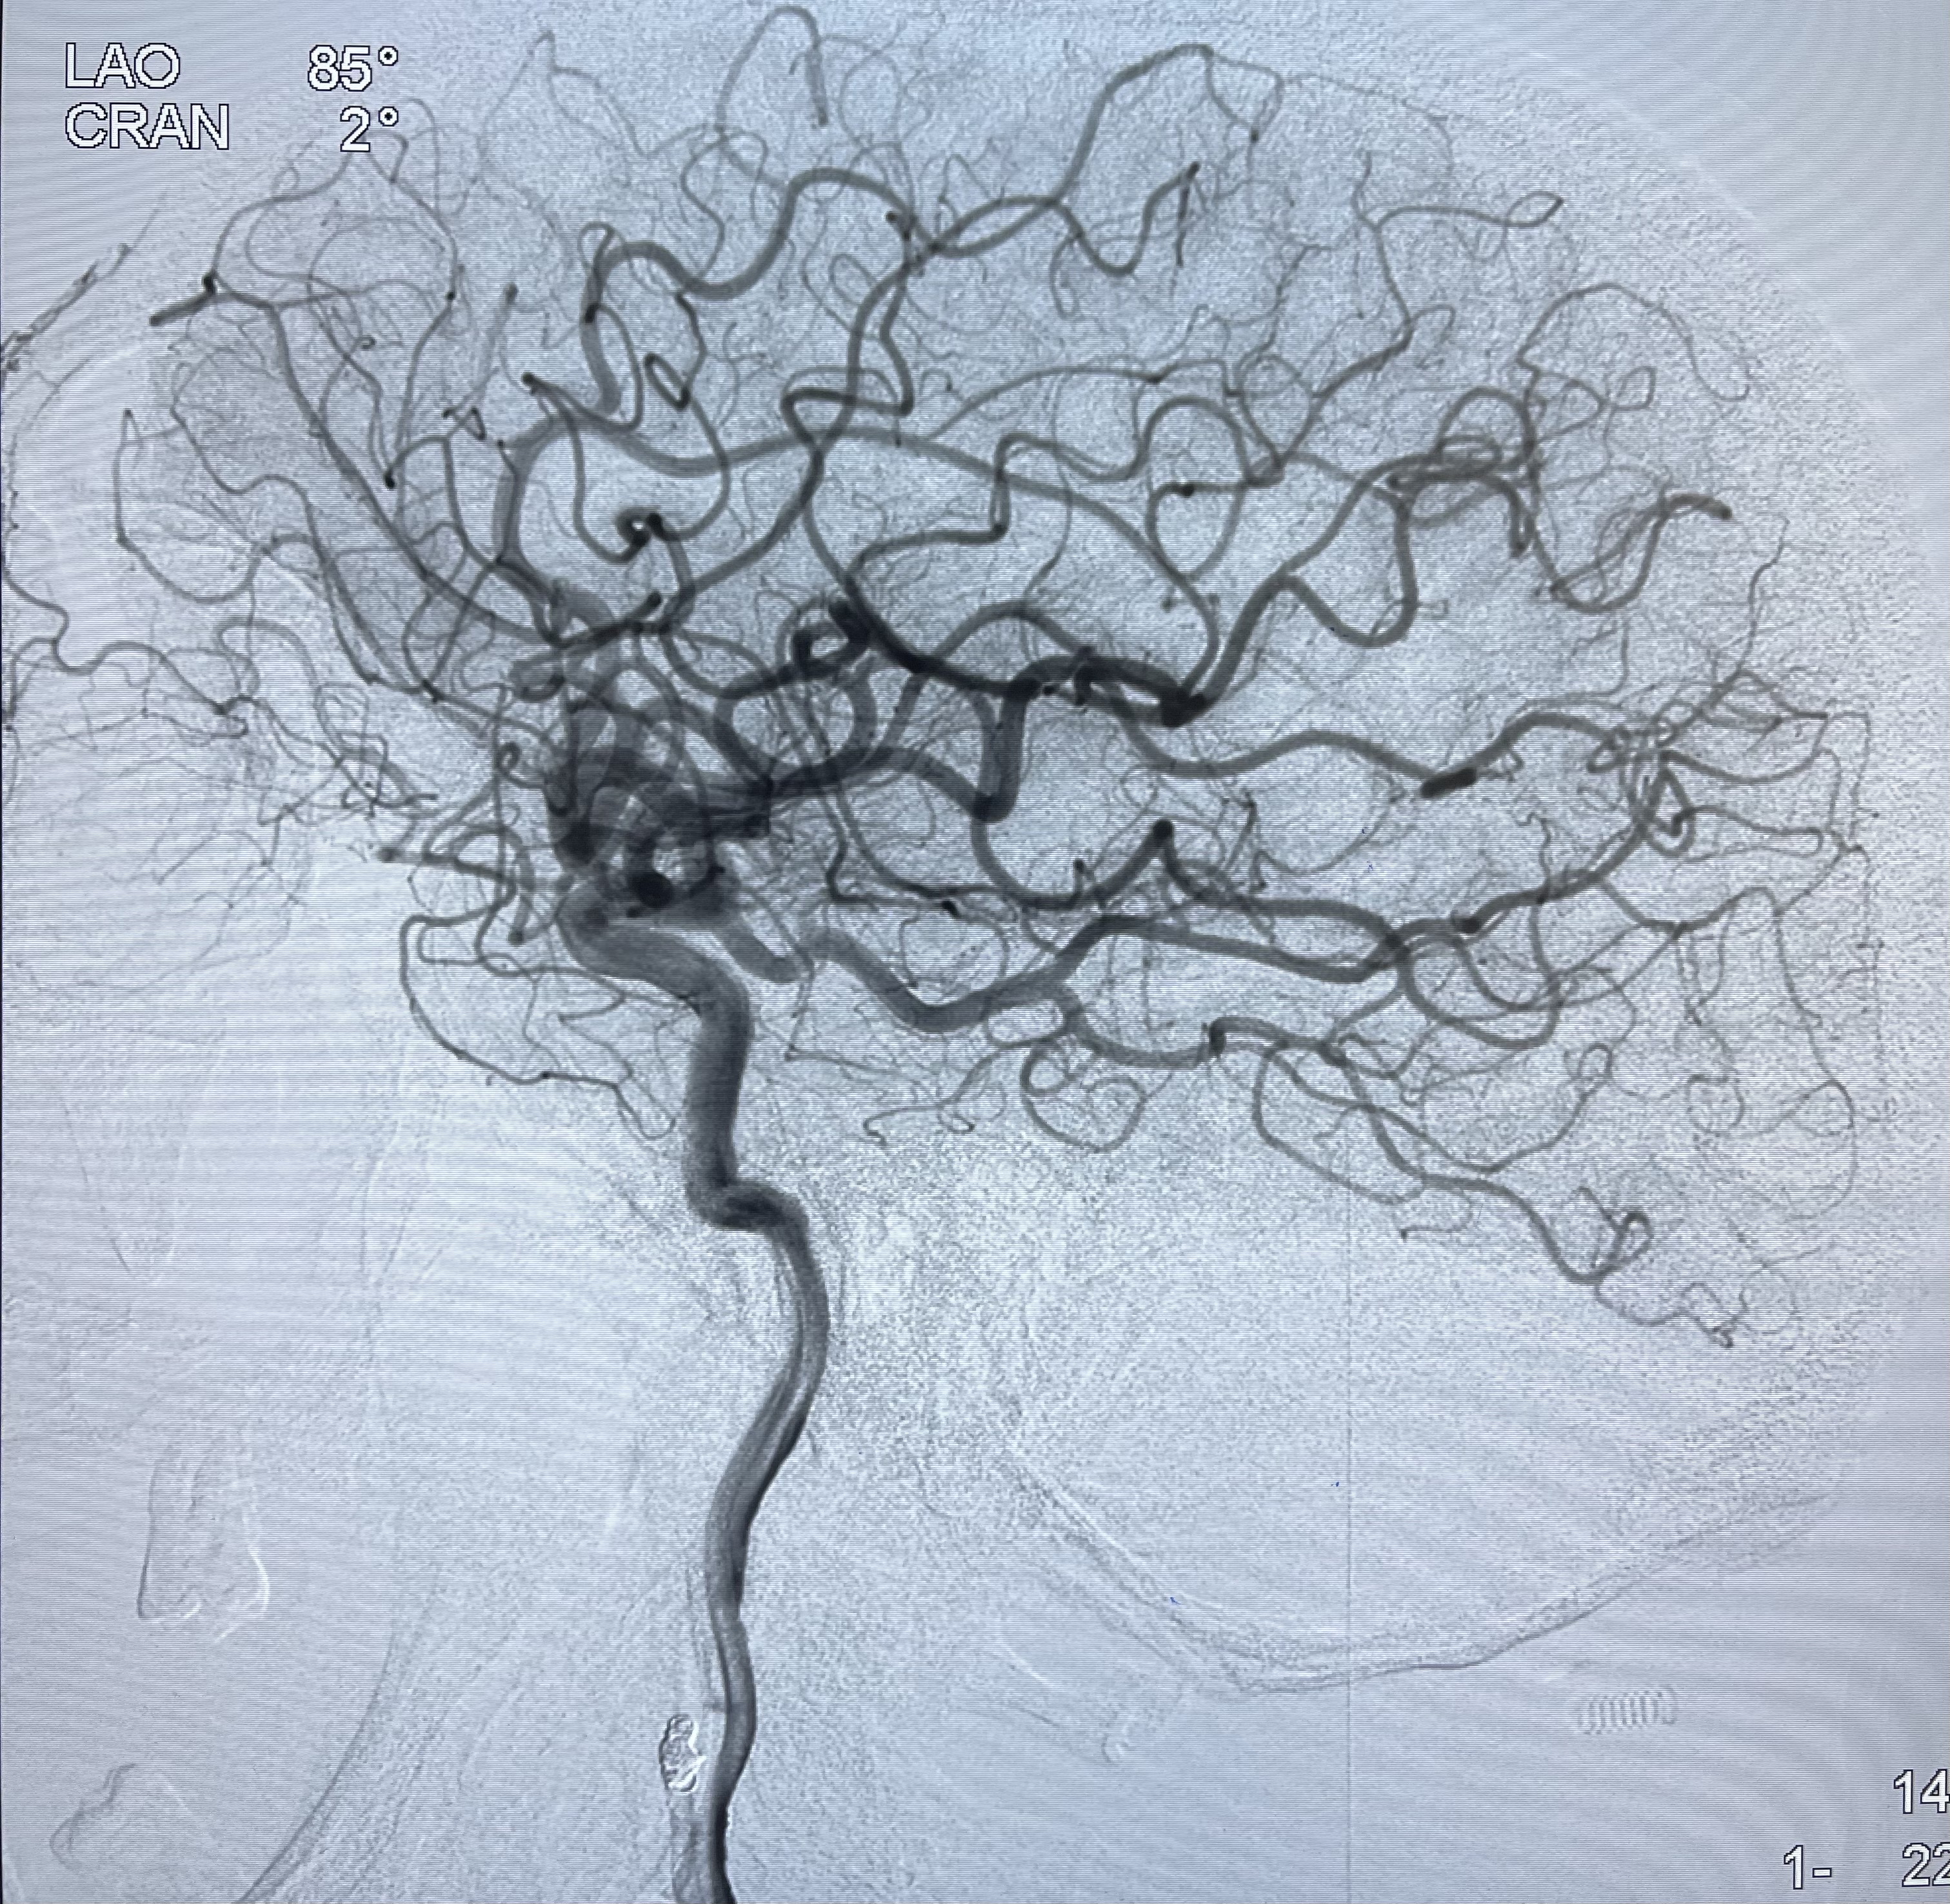

2021-03-08行全脑血管造影

工作角度造影